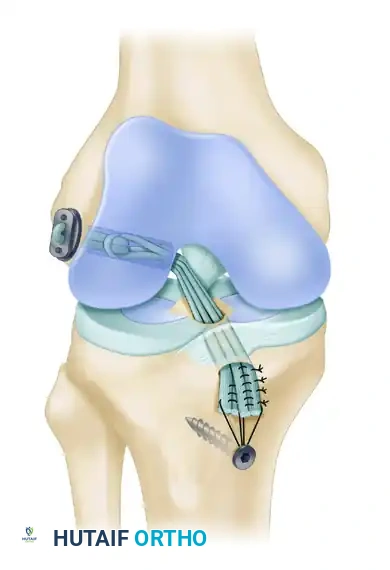

To address this, physeal-sparing techniques have been developed. The transepiphyseal replacement of the anterior cruciate ligament using quadruple hamstring grafts, pioneered and described by Anderson, represents the gold standard for specific subsets of skeletally immature patients. By confining the drill holes entirely within the epiphysis and avoiding the transphyseal route, this technique restores native knee kinematics while mitigating the catastrophic risks of premature physeal closure, angular deformity, and leg-length discrepancy.

The biomechanical goal is to achieve an anatomical footprint reconstruction. However, because the tunnels must remain strictly within the epiphysis, the trajectory of the tunnels differs from adult reconstruction. The femoral tunnel is drilled from the lateral epicondyle directly into the intercondylar notch, while the tibial tunnel is drilled from the medial epiphysis into the tibial footprint.

6. Graft Passage and Proximal Fixation

- EndoButton Selection: Measure the total width of the lateral femoral condyle. Select an appropriate EndoButton continuous loop (Acufex-Smith Nephew, Memphis, TN)—usually 2 to 3 cm—ensuring that approximately 2 cm of the quadruple hamstring graft will remain docked within the lateral femoral condyle.

- Graft Loading: Pass the EndoButton continuous loop around the middle of the doubled tendons, looping it inside itself to secure the tendons proximally.

- Passage: Place a No. 5 FiberWire passing suture into one end of the EndoButton. Use a suture passer to shuttle this suture from anterior to posterior, up through the tibial tunnel, across the joint, and out through the lateral femoral condyle.

- Femoral Fixation: Pull the EndoButton and tendons up through the tibia and out the femoral hole. Because the transepiphyseal femoral hole is larger than the standard EndoButton, an EndoButton washer (Smith & Nephew, Memphis, TN) that is 3 to 4 mm larger than the femoral hole must be placed over the EndoButton. Apply distal tension to the graft, pulling the EndoButton and washer flush against the lateral femoral condyle cortex.

- Tibial Fixation: Position the knee in 10 degrees of flexion. Secure the quadruple hamstring graft distally by tying the No. 5 FiberWire whipstitches tightly over a tibial screw and post.

- Critical Placement: The screw and post must be placed medial to the tibial tubercle apophysis and distal to the proximal tibial physis to avoid growth disturbance.

- Augmentation: If the tendon graft extends out through the anterior tibial drill hole, augment the fixation by suturing the tendon directly to the anterior tibial periosteum using multiple No. 1 Ethibond sutures in a figure-of-eight configuration.